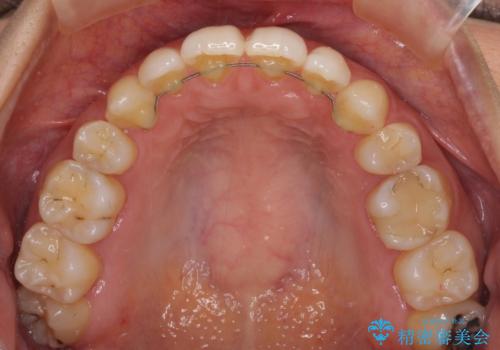

- 以前の矯正治療の後戻りにより、上の前歯にスペースができたことを気にして来院された患者様です。

インビザラインを用いて前歯のスペースを閉じつつ、上下の咬み合わせを構築していくこととしました。

隙間の空いてしまった前歯は、矯正治療で治療を行っても後戻りが起こりやすい傾向にあります。

マウスピースの保定装置をしっかりと装着しても空いてしまうため、細いワイヤーによる保定を併用することで後戻りを防止しています。